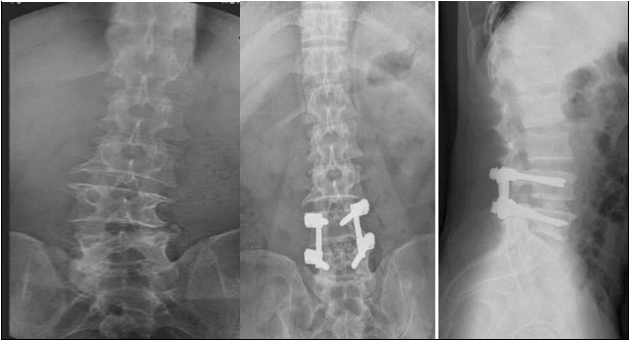

单纯后路椎管减压手术,直视下去除狭窄节段的椎板、棘突等后方附件,扩大骨性椎管,一并摘除间盘,实现神经周围的减压。短期效果理想,但对脊柱后方稳定结构的破坏较大,会加速脊柱退变和侧弯进展。

后路椎管减压+短节段固定,在后路椎管减压的基础上,行病变节段固定,可以稳定脊柱,缓解神经根受压症状,但无法纠正脊柱退变和侧弯,畸形和腰痛无法改善。